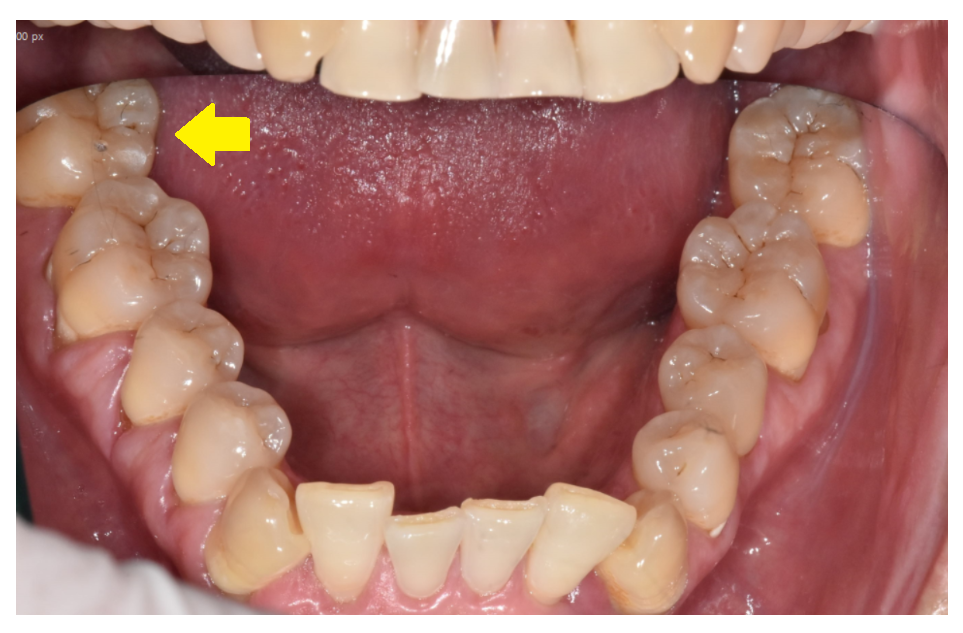

오른쪽 아래 치아

잇몸이 자꾸 욱신거려요

덕풍동 치과를 방문해주신 환자분의 말씀입니다.

x-ray 찍기보다

원장님이 먼저 보고 말씀해달라 하셔서

입안 상태를 먼저 보았습니다.

230206

불편을 호소하신 오른쪽 아래 부분

육안으로는 충치도 없고

깨져 나간 부위도

금이 간 흔적도 없었습니다.

다른 치아와 비교해서 큰 문제가 없었는데요.